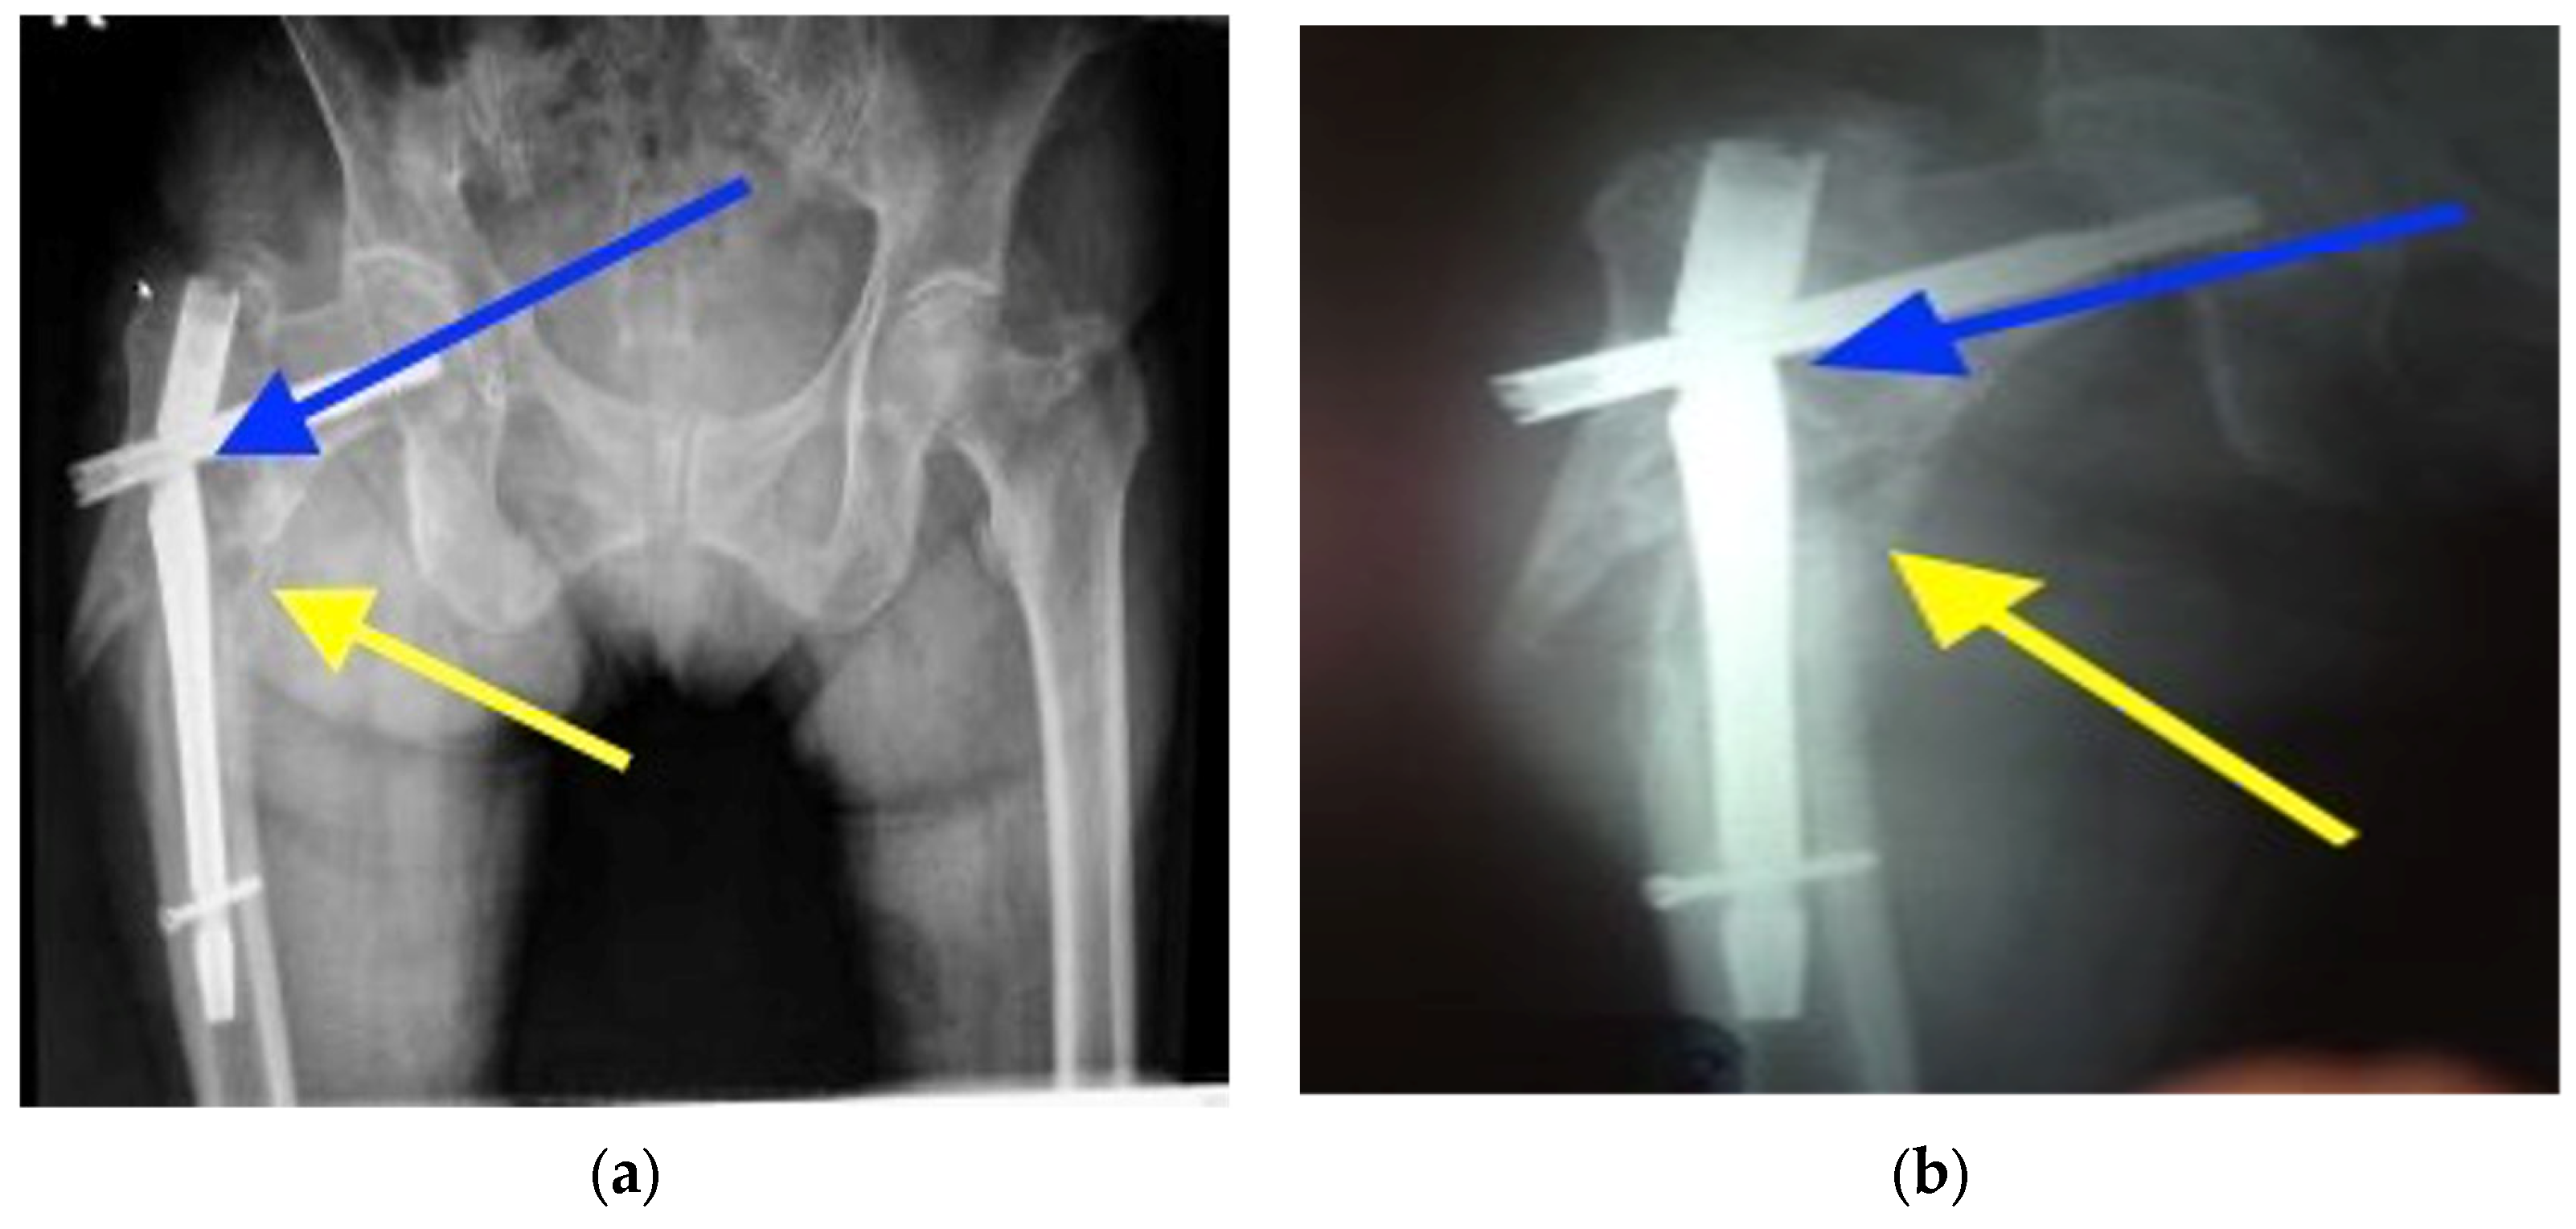

4.1. Clinical Case History of the Failed Gamma Nail

| Radiologic images study | Visualization of the bone and implant. |